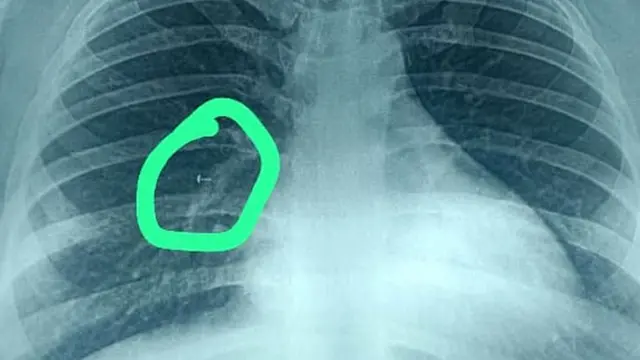

ਜਦੋਂ ਦਵਾਈਆਂ ਨੇ ਕੰਮ ਨਹੀਂ ਕੀਤਾ ਤਾਂ ਉਨ੍ਹਾਂ ਨੇ ਪਲਮਾਲੌਜਿਸਟ ਦੀ ਸਲਾਹ ਲਈ। ਸੀਟੀ ਸਕੈਨ ਵਿੱਚ ਉਨ੍ਹਾਂ ਦੇ ਫੇਫੜੇ ਵਿੱਚ ਕੋਈ ਚੀਜ਼ ਫਸੀ ਹੋਣ ਦਾ ਪਤਾ ਲੱਗਿਆ। ਇਸ ਤੋਂ ਬਾਅਦ ਕੀਤੇ ਗਏ ਐਕਸ-ਰੇ ਨੇ ਸਪੱਸ਼ਟ ਕਰ ਦਿੱਤਾ ਕਿ ਇਹ ਕੀ ਸੀ।

ਨੱਕ ਵਿੱਚੋਂ ਕੋਕੇ ਦੀ ਕੋਲੀ ਨੂੰ ਕਿਵੇਂ ਕੱਢਿਆ ਗਿਆ